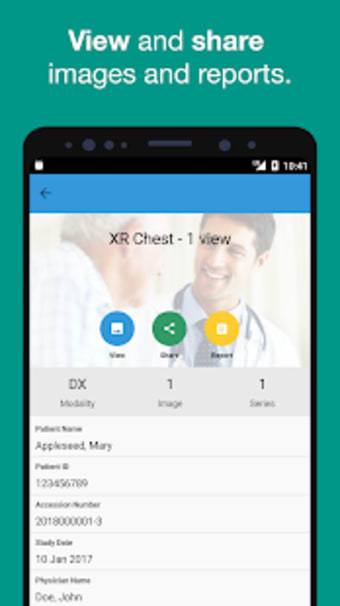

Met Affidea Connect Patient kunt u uw beeldvormingsresultaten bekijken, ze delen met uw zorgverleners en overal en altijd toegang krijgen. De app is gemakkelijk te gebruiken en u kunt er zonder moeite doorheen navigeren. U kunt ook eerdere beeldvormingsresultaten bekijken, waardoor het gemakkelijker wordt om uw voortgang te vergelijken en bij te houden. Over het algemeen is Affidea Connect Patient een geweldige app die u helpt om de controle te houden over uw gezondheidszorg en geïnformeerde beslissingen te nemen over uw gezondheid.